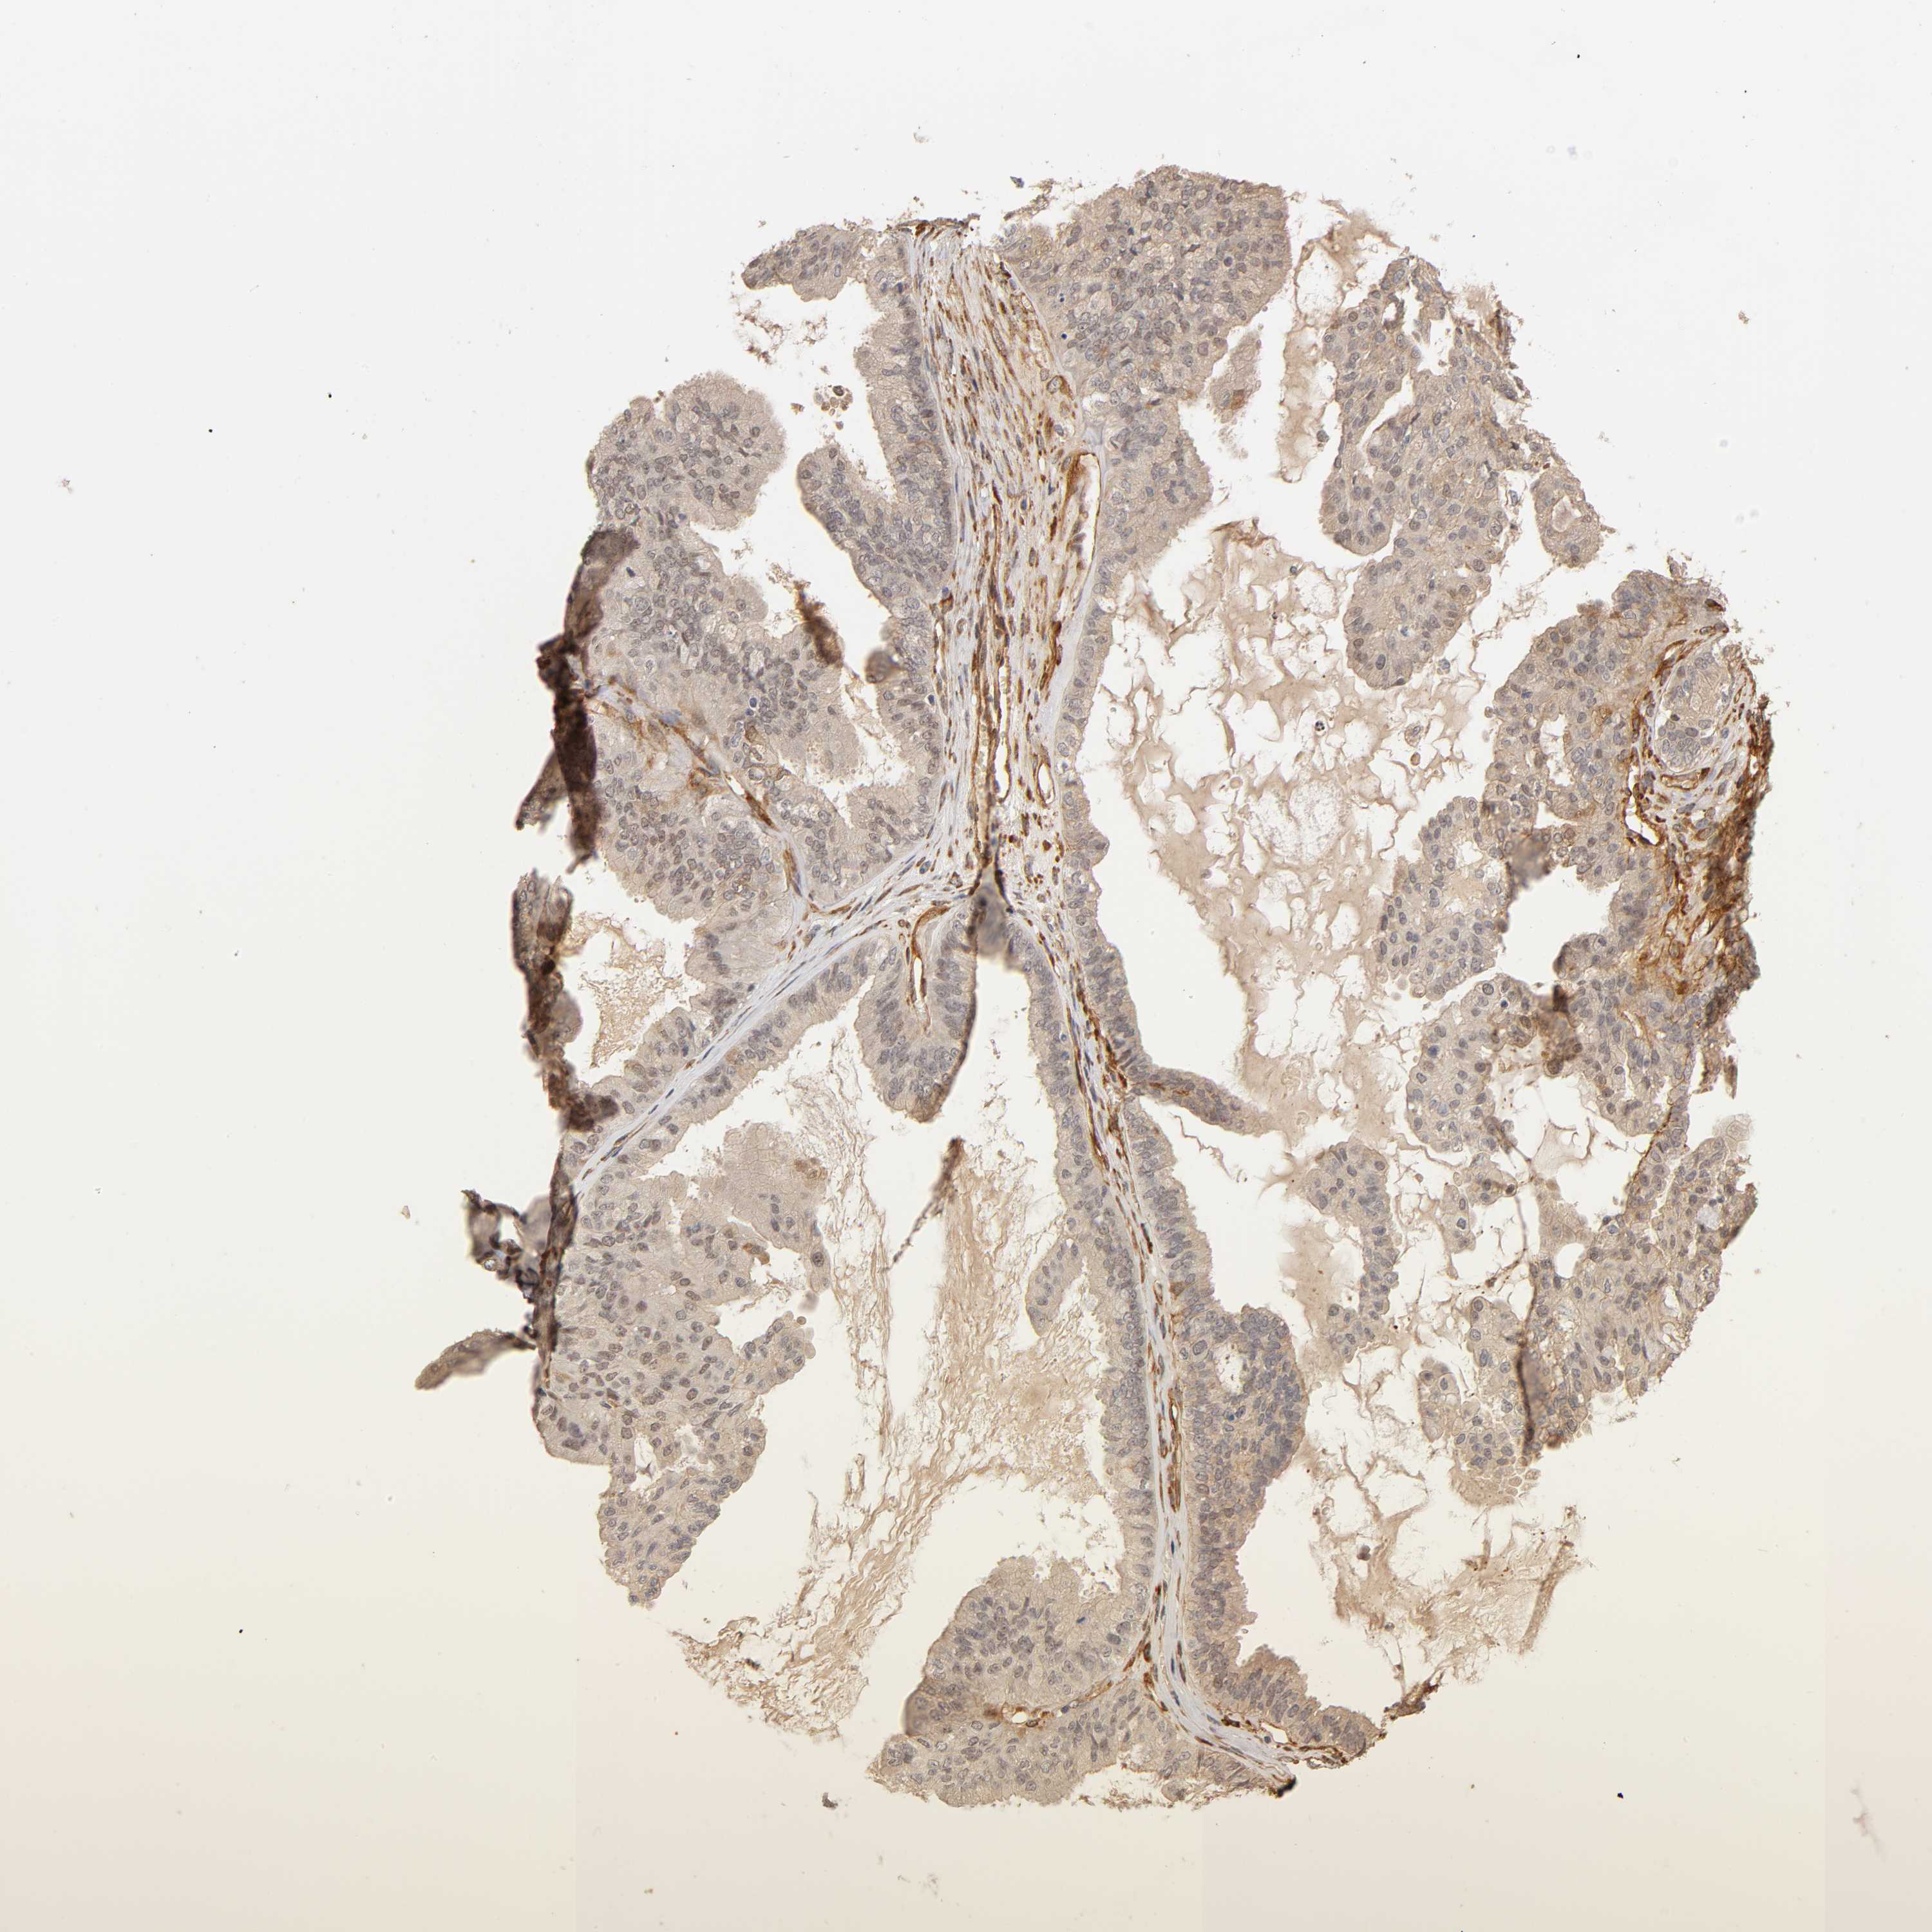

OVARIAN CANCER - Protein expressioni

A mouse-over function shows sample information and annotation data. Click on an image to view it in a full screen mode. Samples can be filtered based on level of antibody staining by selecting one or several of the following categories: high, medium, low and not detected. The assay and annotation is described here.

Note that samples used for immunohistochemistry by the Human Protein Atlas do not correspond to samples in the TCGA dataset.

Antibody stainingi

Antibody staining in the annotated cell types in the current human tissue is reported as not detected, low, medium, or high, based on conventional immunohistochemistry profiling in selected tissues. This score is based on the combination of the staining intensity and fraction of stained cells.

Each image is clickable and will lead to virtual microscopy that enables deeper exploration of all samples and also displays staining intensity scores, fraction scores and subcellular localization as well as patient and tissue information for each sample.

Staining

High

Medium

Low

Not detected

Cystadenocarcinoma, serous, NOS

Cystadenocarcinoma, mucinous, NOS